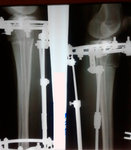

Пациентка - 37 лет.

Диагноз: варусная деформация голеней. Ротация с обеих сторон.

Дата операции - 24.10.2019г.

Дата снятия аппаратов - 22.01.2020

Срок сращения - 89 дней.